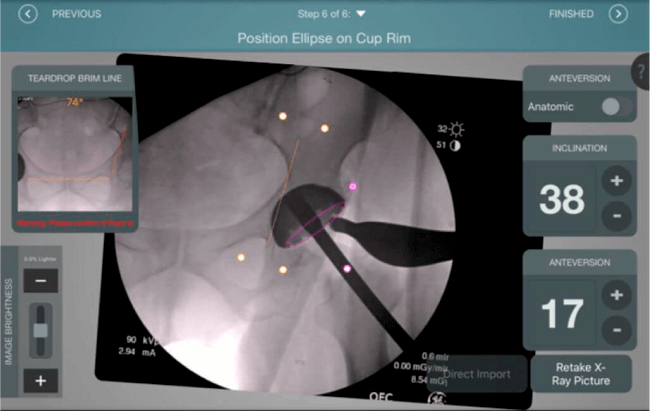

Mayor nivel de información intraoperatoria facilita la colocación correcta de los implantes:

Inclinación y anteversión de la copa acetabular para una correcta colocación del implante.

Verificación de la posición deseada del implante que potencialmente puede ayudar a reducir la probabilidad de dislocación protésica y aumentar la estabilidad de la articulación.